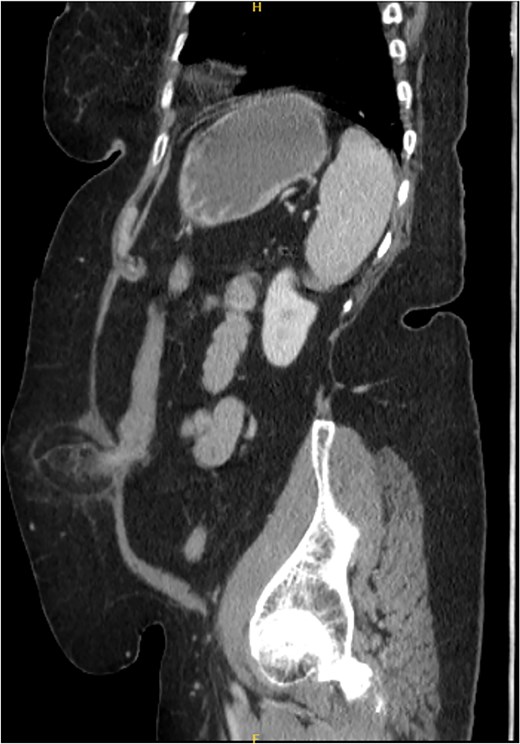

Coronal section of CT abdomen and pelvis showing the ventral hernia.